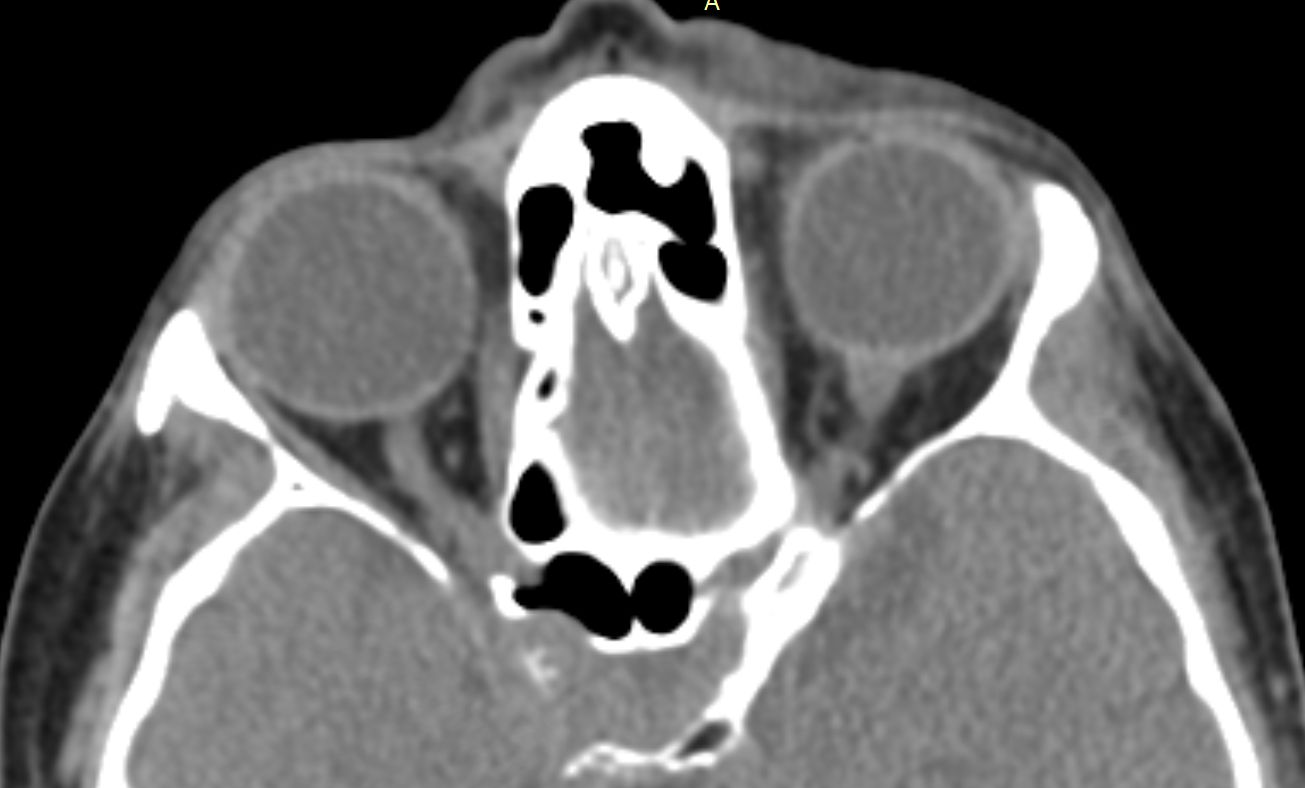

КТ ретроперитонеального фиброза: Изображения и диагностика